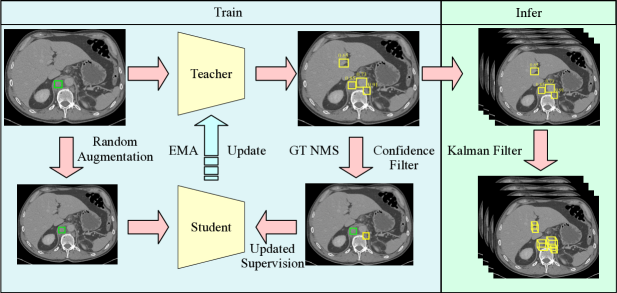

Specifically, our method adopts the teacher-student framework to simultaneously mine unlabeled lesions and train the detector. For each mini-batch, the teacher branch infers the input data and creates a set of predictions. The high-confidence predictions are considered suspicious lesions and are combined with partially-labeled ground truth to train the student branch. The teacher branch maintains an exponential moving average (EMA) of the student’s parameters and is used as the final output model. The main contributions are summarized as follows: (1)We propose a novel end-to-end framework to address the missing annotation problem in the universal lesion detection task. (2) We systematically compared different policies for dealing with the mined suspicious regions. (3) The proposed framework is highly efficient and achieves the state-of-the-art lesion detection performance on the fully-annotated test set of the DeepLesion dataset.

Fig. 2 illustrates the overview of our lesion mining and detection model. It follows the teacher-student paradigm [15], consisting of two detection branches with the same structure. The parameters of the student branch are updated by gradient back-propagation under the supervision of the partially labeled ground truth and the mined suspicious lesions from the teacher branch. The teacher branch maintains an exponential moving average (EMA) of the student’s parameters. We use Faster R-CNN [16] as our lesion detector framework.

Given the partially annotated dataset , where represents the image and is the available lesion annotations, denotes the missing annotations that are not accessible. For the generation of suspecious lesions, at each mini-batch, the teacher branch first infers the batch inputs to give a set of predictions . Next, the predictions are compared with the available ground truth by their intersection over union (IoU) values, we then remove the predictions which have IoU larger than a threshold with any ground truth. For simplicity, we use , and to denote the batch predictions , available ground truth and unlabeled ground truth . The remaining predictions can be written as . This process can be easily implemented using Non-Maximum Suppression (NMS) operation on the predictions and ground truth, we name it as GT NMS operation. Finally, we filter out the predictions with confidence scores lower than threshold . The remaining predictions are represented as and will be served as mined lesions to feed the student branch.

We use the teacher branch as our final model because its EMA update strategy has a model ensemble effect [15] which can give better results. It is vital for the ensemble model to have diverse components. However, the commonly used learning rate decay policy will make the student model converge to similar parameters. Therefore, we use a constant learning rate without decay in our training. For inference, We use the same Kalman filter as lesion harvester [10] for tracing the 2d predictions on each slice to the 3d lesion bounding boxes.